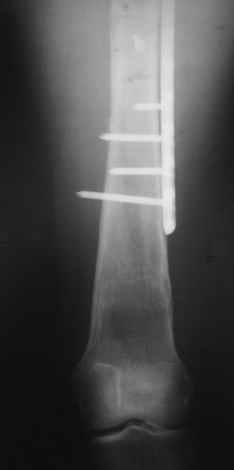

Прошу прощения, со снимками глюк произошел. Высылаю. С уважением Евгений У.

Получилось очень симпатично, мои поздравления. А можно фото конечности без наклеек посмотреть?

И межфрагментарный винт на диафизе - так ли он нужен при выбранном варианте остеосинтеза с относительной стабильностью?

Но в люом случае, что сделано - то сделано, и сделанное выглядит вполне обнадеживающе, так что еще раз поздравляю коллег с успешным выходом из непростой ситуации.